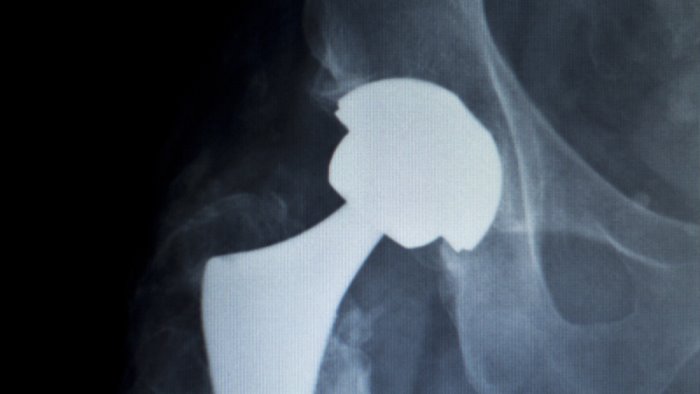

Una protesi non è mai un oggetto da installare, ma un’estensione del corpo di chi la riceve. Per questo la scelta dei materiali — ceramica, polietilene, metallo — viene calibrata con attenzione in base all’età, alla struttura fisica, al grado di attività e alle aspettative di ciascuno.

Il Dr. Caviglia integra anche tecnologie moderne come sistemi computer-assistiti, navigazione e metodiche avanzate per la pianificazione pre-operatoria. L’obiettivo è semplice: precisione assoluta. Una protesi posizionata nel punto perfetto funziona meglio e dura di più.